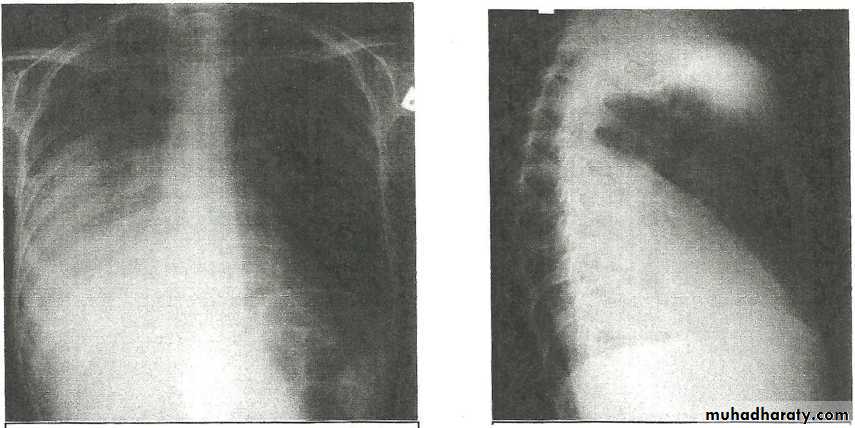

Pneumomediastinum.

Vertical dark (lucent) lines representing air within the mediastinum are usually seen at or above the level of the aortic arch.

On the posteroanterior view (A), these can be seen extending up into the lower cervical soft tissues (arrows).

On the lateral view (B), dark linear air collections can be seen in front of and behind the trachea.